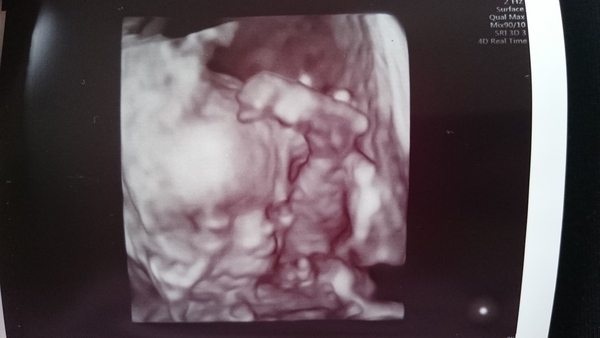

For anyone not in the fb group, mini pretzel is a girl and all looks good on 20 wk scan. Still thrilled. See freaky 3d scan pic attached of her yoga pose.